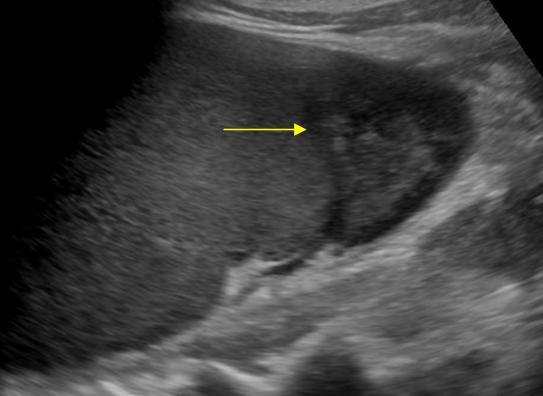

Nhồi máu lách

» Thông tin: Nam giới – 74 tuổi.

» Lâm sàng: Đau mạn sườn trái.